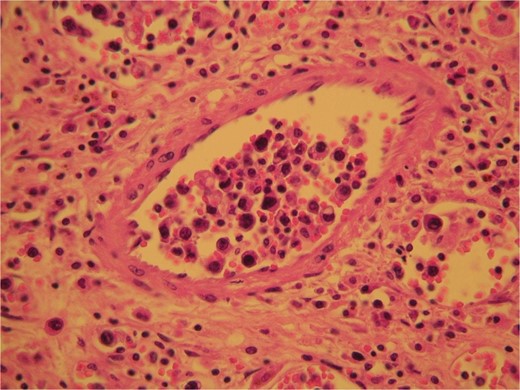

The surgical specimen consisted of a solid, soft, tan colored 10.5 × 7 × 4 cm tumor (Fig. 2). H&E sections showed a neoplasm confined to the adrenal gland consisting of tumor cells located inside dilated, thin-walled vascular spaces (Fig. 3). The neoplastic cells were large with irregular nuclei that exhibited atypia and had one or more nucleoli. Necroses were evident. Immunohistochemical stains showed that the neoplastic cells were positive for Vimentin, LCA, CD20 (Fig. 4), CD79a (Fig. 5) and negative for Cyrokeratins 7, 8, 18, 19, HMB45, S100, CD30, Myeloperoxidase, Inhibin, CD3, CD5, CD56, Chromogranin, CD31 and CD34. These findings were consisted with the diagnosis of primary adrenal intravascular large B-cell lymphoma. The patient was then referred to a Hematology Unit for further staging and treatment. Six cycles of R-CHOP were given lasting 21 days each: (Rituximab 375 mg/m2 iv (D1), Cyclophosphamide 750 mg/m2 iv (D1), Doxorubicin 50 mg/m2 iv (D1), Vincristine 1 mg/m2 iv (D1), P: Prednizolone 100 mg iv on D1-D5). After the completion of this chemotherapeutic regimen, a PET scan showed complete remission of the disease. Thereafter, the follow-up schedule consisted of CT studies every 6 months for 2 years and once annually, for the next 3 years. Despite the dismal prognosis, the patient 6 years after the initial diagnosis remains alive and in complete remission.

H&E sections revealed the presence of tumor cells inside dilated, thin-walled vascular spaces exhibiting minimal cytoplasm and irregular nuclei with atypia.